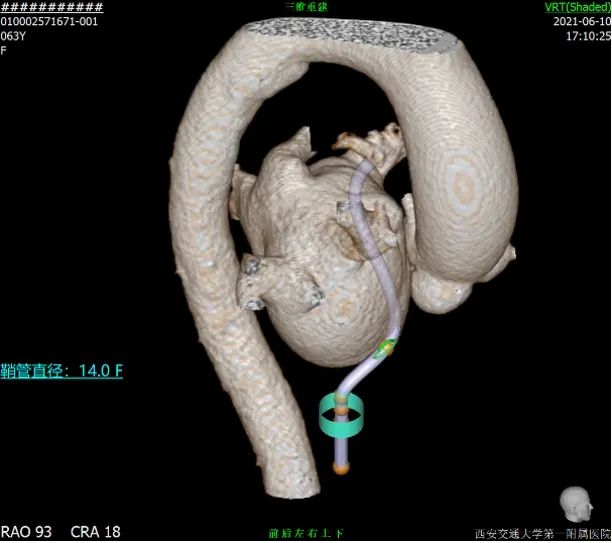

患者TEE检查心耳内无血栓,TEE提示为反鸡翅可能,CTA重建心耳后为反鸡翅型,根据术前入路模拟,考虑穿刺点应偏下稍靠前,根据心脏CT及TEE评估结果来看,左心耳梳状肌发达,开口椭圆形,直径17mm-21mm,考虑24mm WATCHMAN封堵植入,在封堵轴线选择上应以上叶为首选。

拟选封堵器类型及型号:根据术前TEE和CT评估结果,拟采用WATCHAMN 24mm封堵器。

手术难点:该患者心耳特点为低位心耳、呈反鸡翅型,因此穿刺位置与常规相比需要靠下且偏前。另该患者心耳深度稍浅,若走下叶封堵可能出现深度不够,露肩较多的情况,因此尽量将鞘管送入上叶进行封堵。